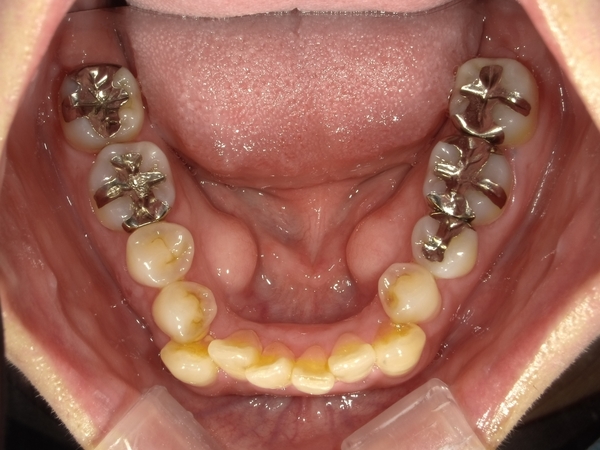

ガタガタとした歯並びや八重歯(叢生)CASE71